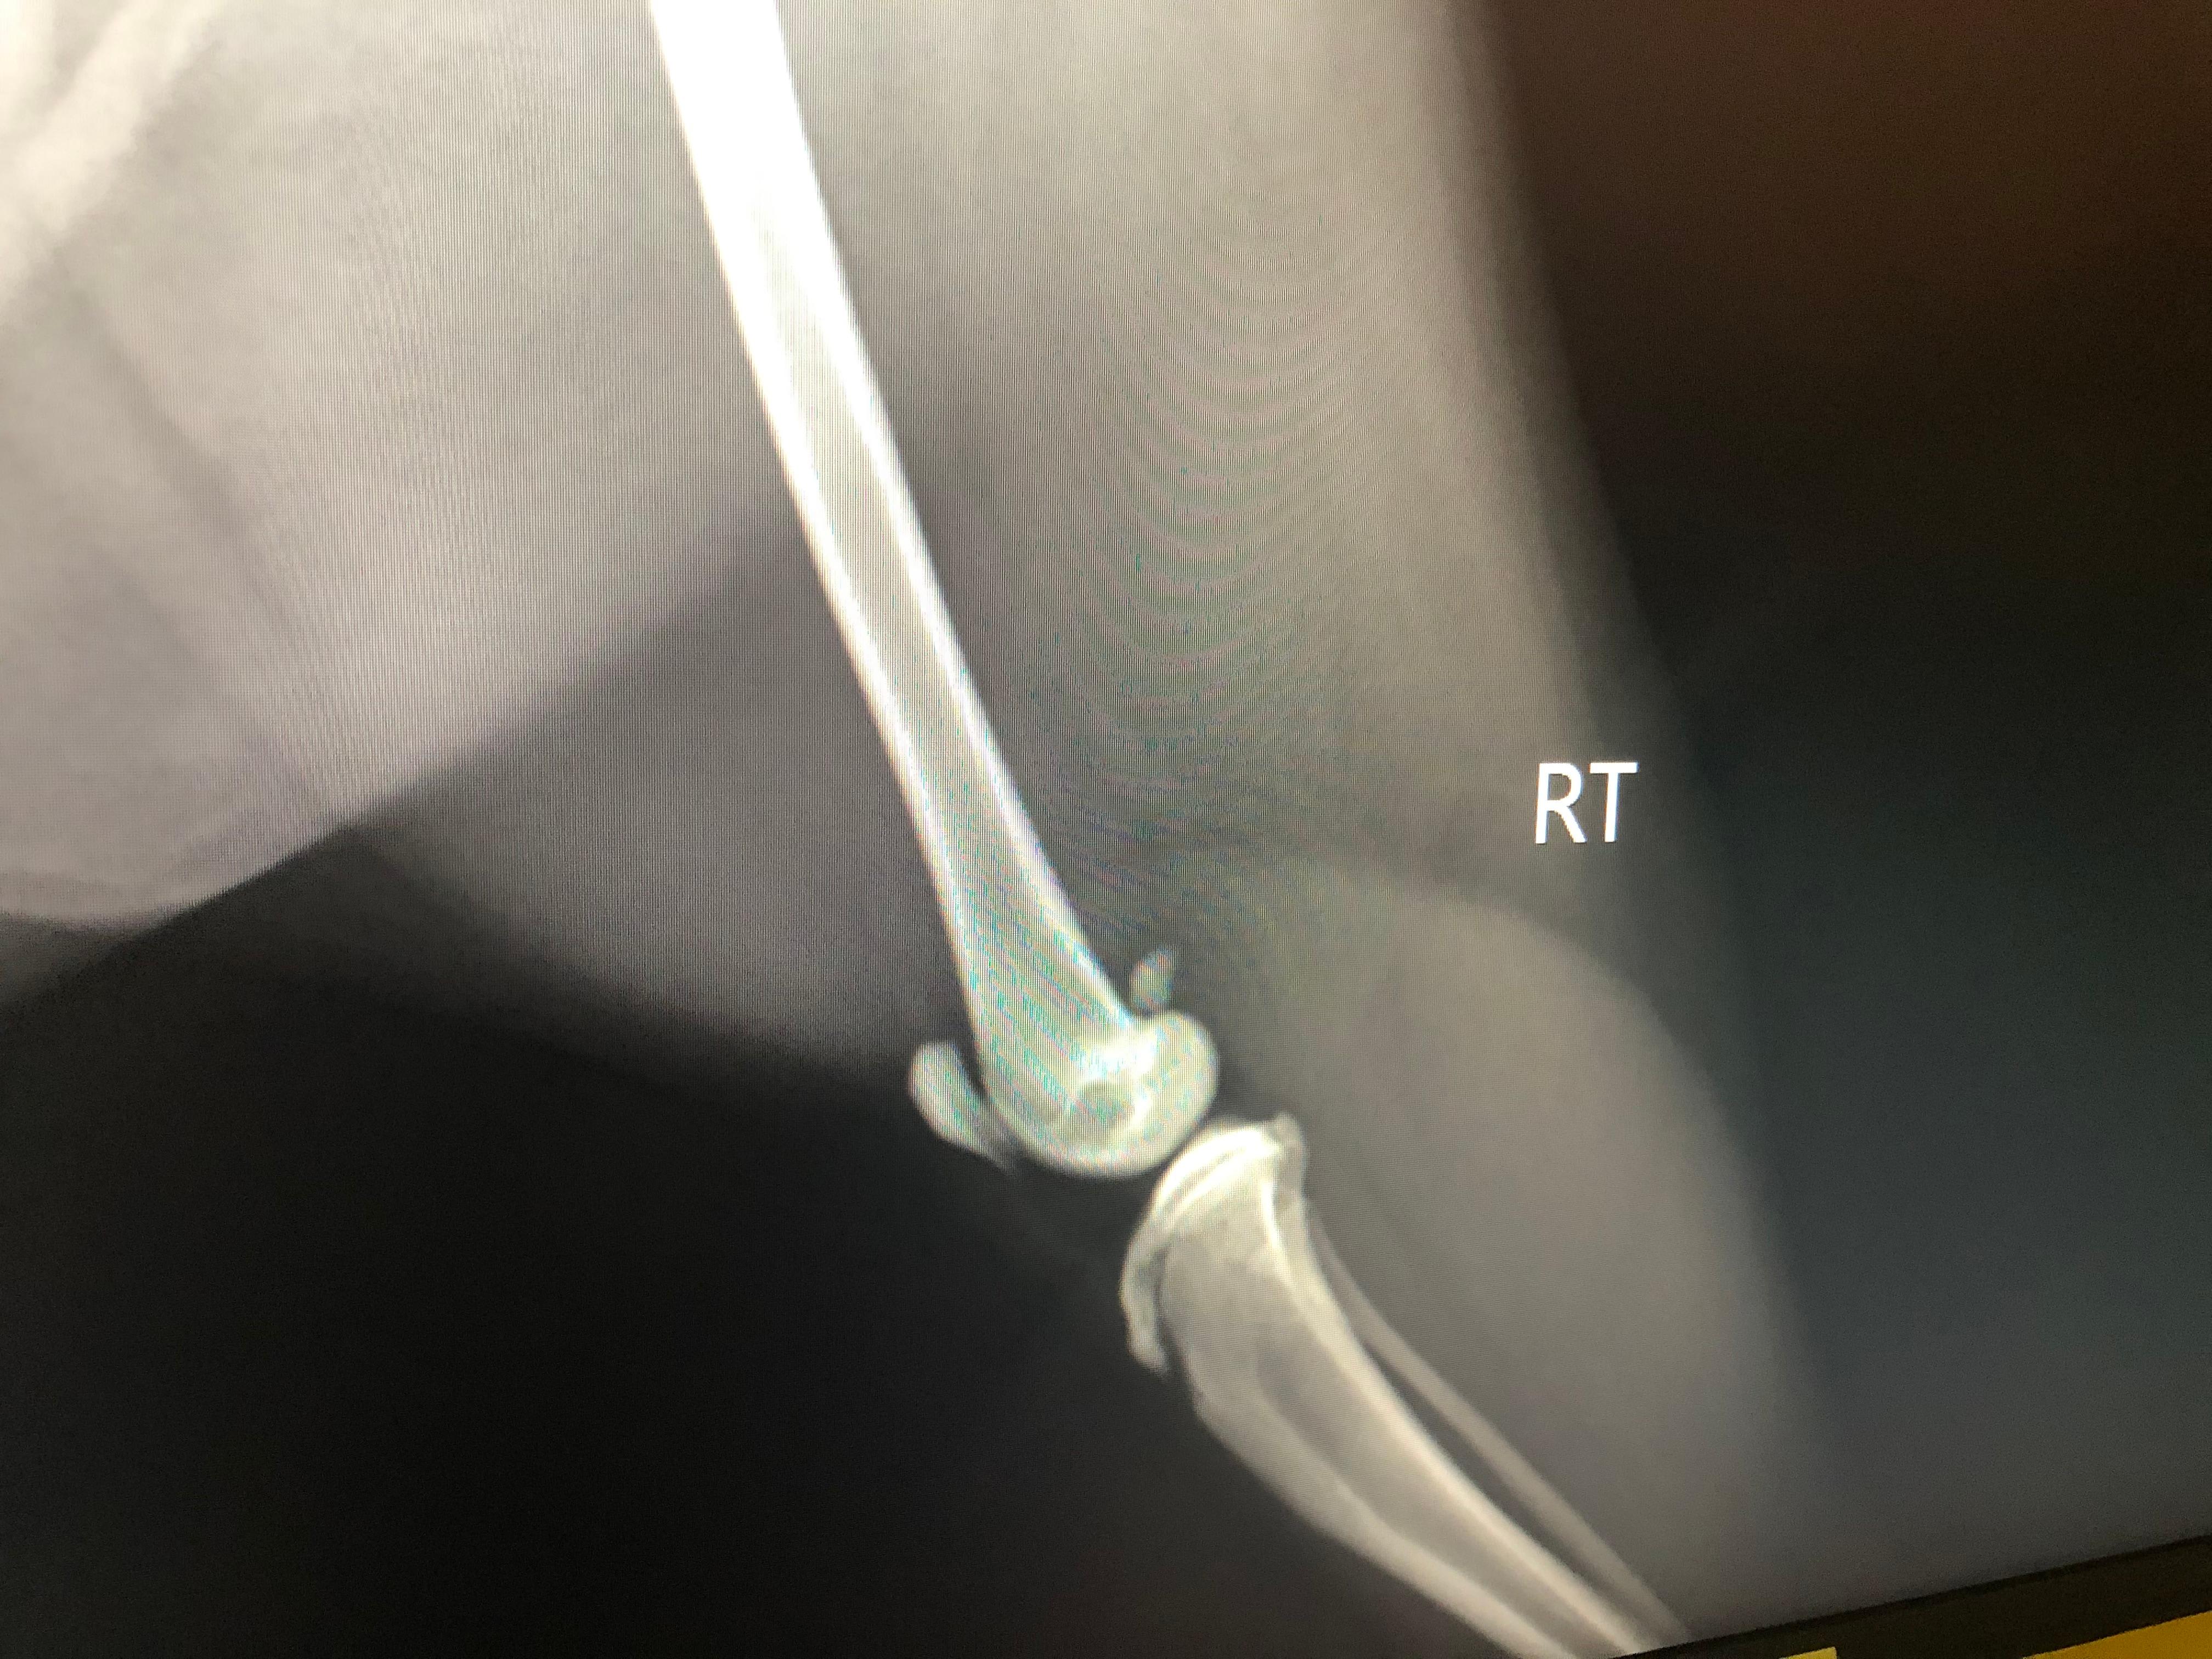

Our cat has been limping for days we took him for X-rays and they want him to see an orthopedic surgeon. Is there anyway you can tell me what is wrong and what the estimated cost or what the procedure would be?

How old is he? If he is past 1 year old, I would be concerned that he may have a fracture of the tibial crest. That is the large bone below the knee. The hips also don't look 100% normal. Without doing an exam on him myself and knowing exactly where he is painful, it is difficult for me to just look at the radiographs and give you a diagnosis. Also, every veterinary surgeon charges differently for different procedures and it is also very depending on location and cost of living. My advice to you would be to go in for the consultation with the surgeon so they can give you more details on what is wrong with him and the best course of treatment. Be sure to ask for estimates for the procedure and if you cannot afford what they are recommending, simply ask what the next best, more affordable option would be. Cats are quite resilient and sometimes they can heal with strict confinement, but I would see what the surgeon thinks. I hope this helps and he starts to feel better soon.